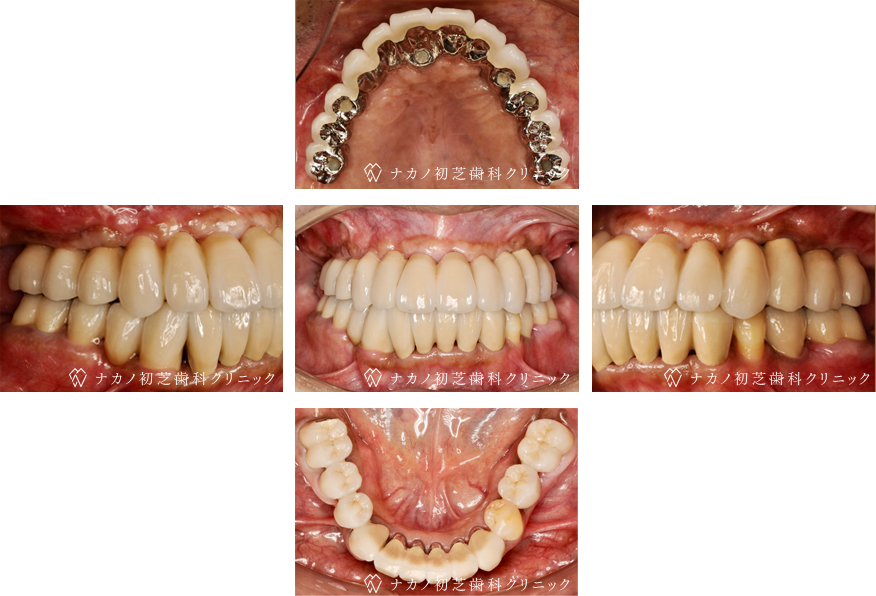

インプラント・13本 (60代女性)

BEFORE

AFTER

年齢 60代女性

治療内容 インプラント治療13本(骨造成の併用)

インプラント治療とは、歯を抜いた所にチタン製の人工歯根を埋入し、その上に歯を入れる方法です。骨を増やすことで、より審美的に治療が出来ました。費用 1本 400,000円(税込 440,000円)

リスク・副作用

腫れ・疼痛・違和感を感じるなどの症状を生じることがあります。